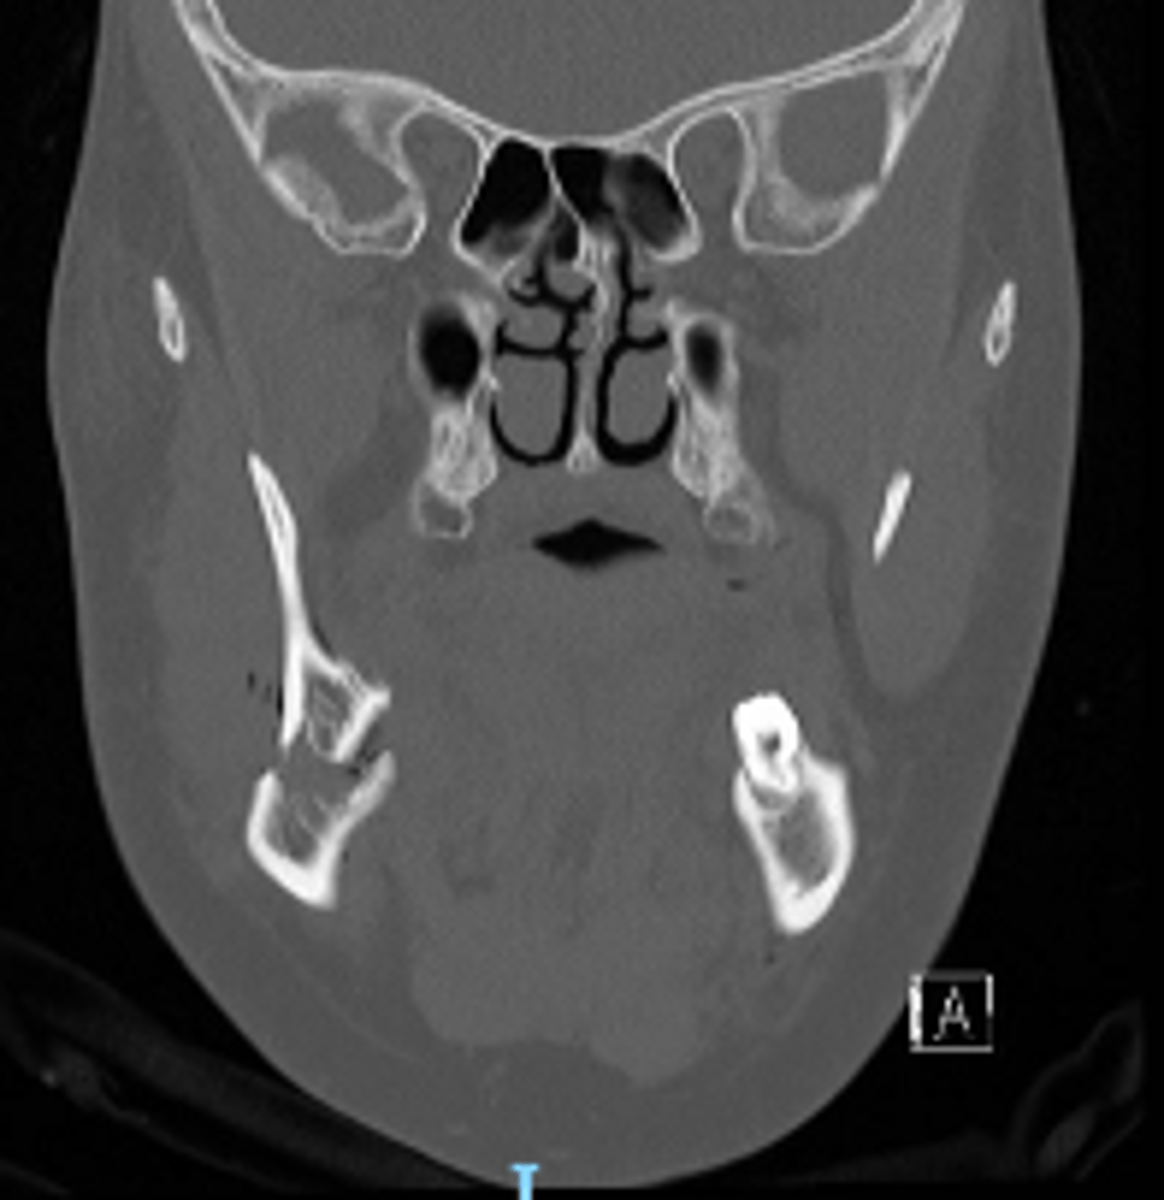

coronal plane

ID the CT view: